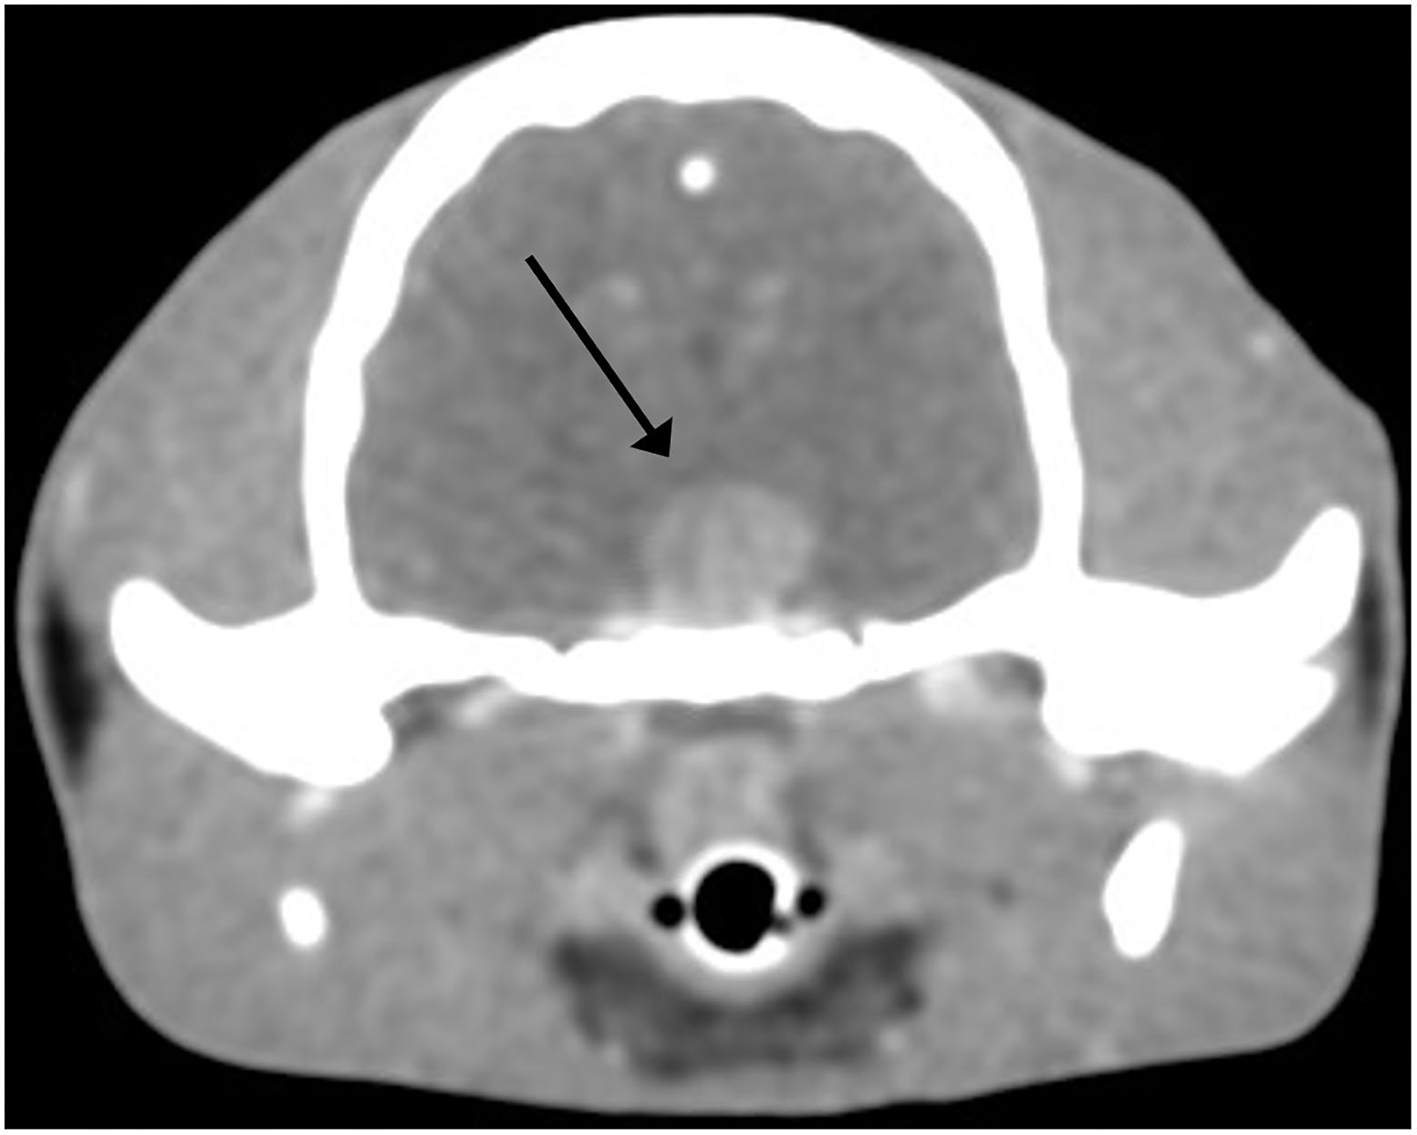

Pre-surgical transverse contrast-enhanced CT images of the brain revealed a hyperintense large ovoid-shaped mass in the area of the pituitary gland measuring 8.6 by 8.3 by 6.8 mm (Figure 1).

Pituitary adenoma, cat. Postcontrast transverse CT image of the skull in soft tissue window. An 8.6 by 8.3 by 6.8 mm mass (arrow) is noted at the anatomical region of the pituitary gland. A slice thickness of 0.62 mm was used.